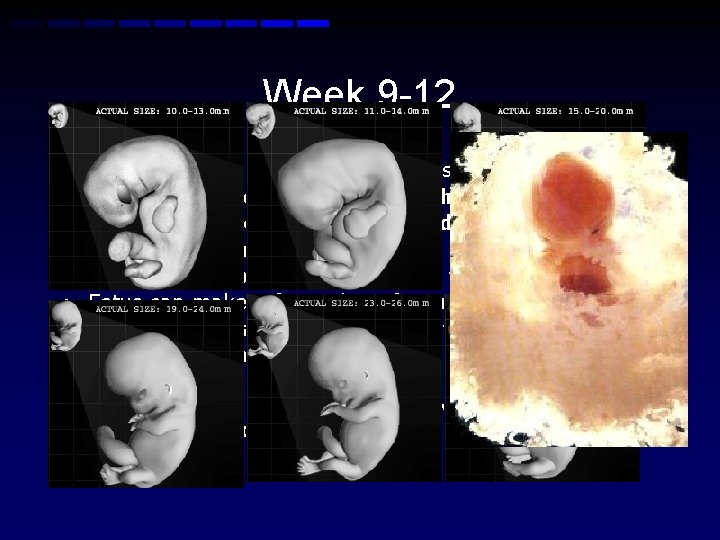

Week 9 -12 • • • Fetus reaches a length of 3. 2 inches Head comprises nearly half of the fetus' size Development of four-chambered heart Fingernails formation begins Tooth buds appear for the baby teeth Fetus can make a fist with its fingers Genitals appear well differentiated Vocal cords can make sounds Bone hardening begins First detectable brain waves-Involuntary movements possible